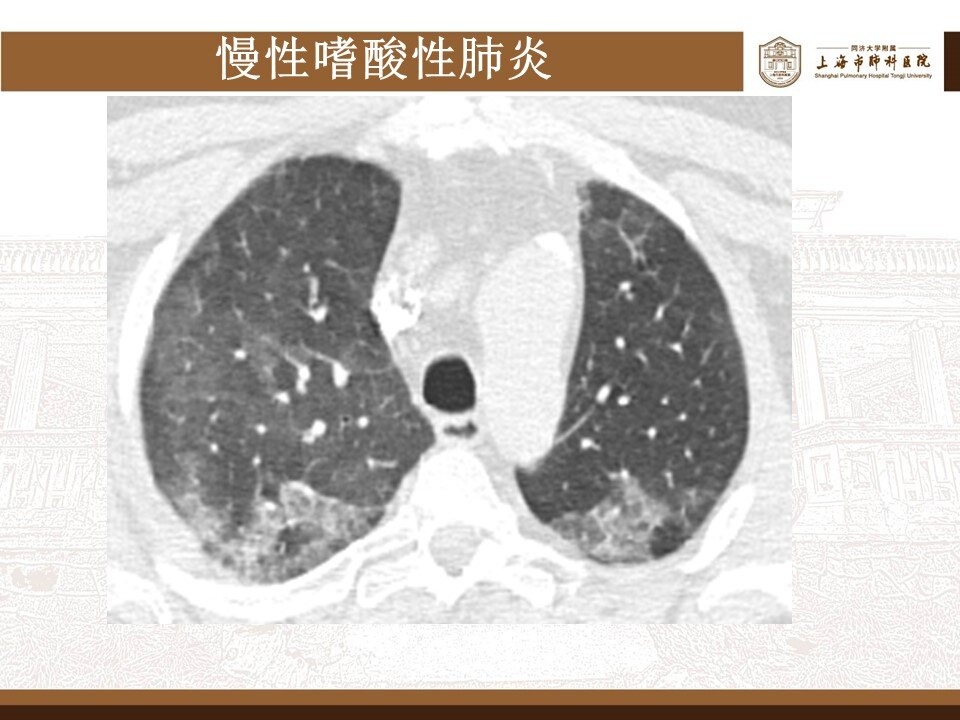

其实,这波omicron感染,确实肺炎比例比想象中要高,但很多都不会是大白肺,多数表现为双肺散发磨玻璃影,当然,也有单独的磨玻璃结节,特别容易表现为混合密度磨玻璃结节。其实很多新发的磨玻璃结节都是新冠肺炎,不用过于紧张,如果感染面积不大,一般临床上,也不需要特异性治疗,休息观察就行了。